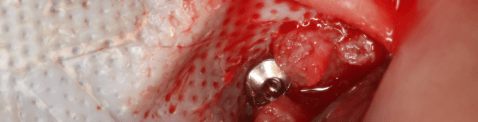

●第十三章植體周圍炎,邀請到這個領域文獻非常多的Frank Schwarz。案例分析、缺損分類、清創植體步驟,都有。很認同Schwarz治療植體周圍炎的想法。簡單說,若決定留下植體,骨再生機率低的植體表面,會做implantoplasty,剩下的可再生區域,再補骨之。不過我發現這章的案例,很多假牙型態,對牙周清潔不易,似乎Schwarz在無法改變假牙的狀態下,進行補救手術,有點可惜。若能有夠多長期追蹤,這樣的疑惑會小一點。